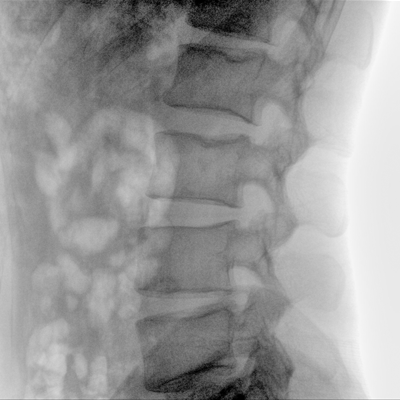

可用于常規(guī)的外周血管介入手術,設備的移動性好,對手術室空間要求低,可滿足長時間X光透視的需求,且增加了獨特的血管影像處理功能,是開展介入手術的理想設備。

優(yōu)質平板探測器、可靈活升降調節(jié)SID、獨特圖像處理系統(tǒng)、高品質濾線柵,大視野成像清晰不失真。

采用智能劑量控制技術,可根據(jù)不同體型和不同部位,準確調節(jié)投照劑量。使操作者在任何使用環(huán)境下,都能實現(xiàn)低劑量、診視圖像清晰的效果。